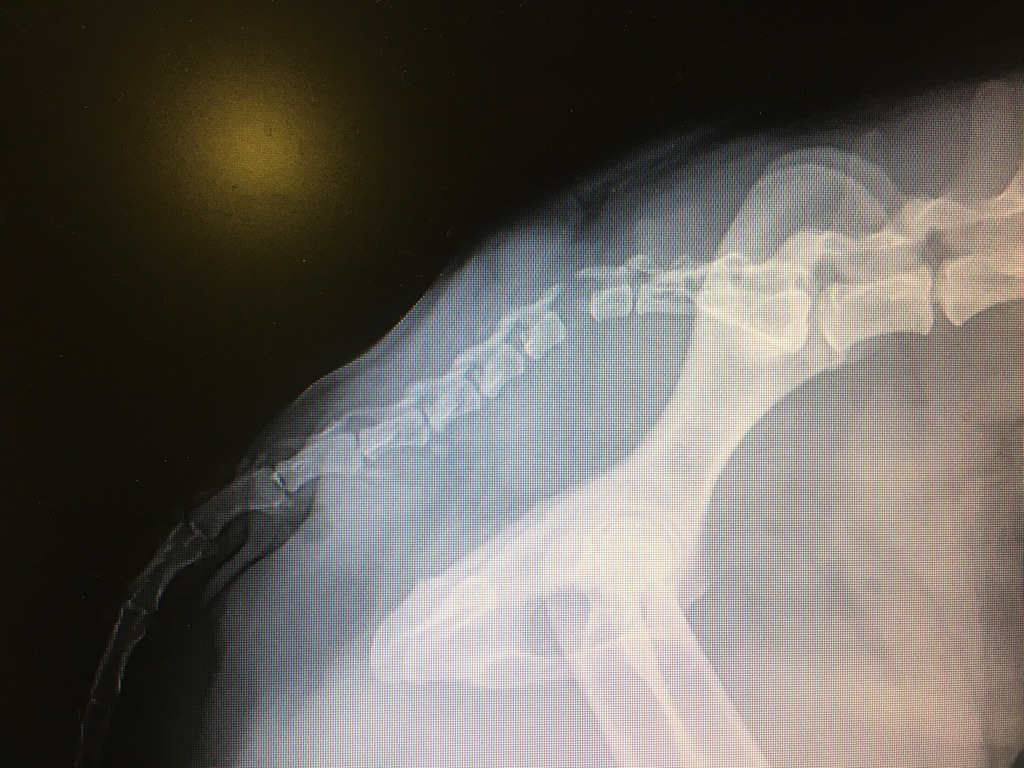

We had a great time over the next couple months with interesting cases and fantastic coworkers. We were only meant to stay 2 months, but decided to extend our contract another 2 months. Here’s a collection of our day-to-day and some crazy things we’ve seen along the way.